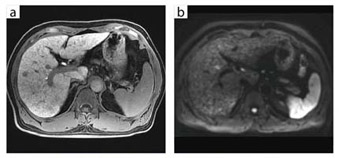

●肝臓への臨床応用 LAVA-FLEX+32chボディアレイコイル

1.1.5Tとの比較と3Tのメリット

谷本:Discovery MR750には,ピクセルごとの局所磁場不均一を計算して再構成することでアーチファクトを抑制する“LAVA-FLEX”というパルス系列が搭載されていますが,肝臓撮像時にLAVA-FLEXを使用することで,きわめて高画質が得られています。1.5Tで使用していたLAVAと比較すると,脂肪がより均一に抑制されますので,造影検査においては非常に有利ですし,T2強調画像でも画質が大幅に向上しています。

また,肝臓の撮像時に最も大事なのはスライス厚とマトリックス数ですが,1.5Tでは,スライス厚を薄くしてマトリックス数を増やすとS/Nはかなり低下してしまいます。しかし,3Tの場合はもともとS/Nが高いため,スライス厚を薄くしてもマトリックス数が増やせるわけです。

拡散強調画像については, 3Tでは1.5Tよりも描出能が低下するというのが一般的な見方でした。しかし,Discovery MR750の場合,1.5TよりもはるかにS/Nの高い明瞭な画像が撮像できる機会が増えました。当院では現在,肝臓の拡散強調画像は5mmスライス厚で撮像していますが,2〜3mm程度の転移も見つかるようになりました。また,当院の場合b値は,1.5Tでは肝臓は600,膵臓は1000に設定しています。しかし3Tでは,高いS/Nを生かして,肝臓も膵臓もb値を1000に設定しました。これにより,正常組織の信号が抑制されてコントラスト分解能が向上し,T2 shine-throughが減少するというメリットが得られています。

1.5Tと3Tでは,T1コントラストの違いも当初は指摘されていましたが,Discovery MR750では1.5Tとまったく変わらず,むしろ向上しています。

2.撮像のポイント

谷本:3T MRIの場合,磁場強度の高さを画質の精度に生かすか,撮像時間の短縮に生かすかということがありますが,当院では,例えばGd-EOB-DTPA造影検査などは基本的に1.5Tと同じプロトコルで撮像しています。ただ,造影前後に拡散強調画像を2回撮るようになったため,1.5Tより5〜10分ほど検査時間が延長しています。今は,1件あたりの検査時間は約40分とし,非常にていねいな検査を心がけています。

3.32chボディアレイコイルの有用性

谷本:体幹部の撮像は,基本的にはすべて32chボディアレイコイルを使用しています。上腹部と骨盤部が同時にスキャンできますので,特に特殊検査では非常に有利です。例えば,尿路の撮像では,腎臓から膀胱までを一度にスキャンしますが,広範囲でも磁場均一性に優れた高空間分解能画像が得られるようになりました。

また,肝臓検査において,当院では,MRIは最終診断法に位置付けています。MRIは被ばくもないですし,コントラスト分解能はCTよりも圧倒的に高いので,CTで鑑別がつかない場合に一歩進めた診断ができます。その際,3T MRIで1.5T MRIよりも高い診断能を得るために,32chボディアレイコイルとLAVA-FLEXの組み合わせは強力な武器となります。RF送信のドライブポイント(給電点)が4つある“4ポイントドライブ”という新技術によってRFのペネトレーションが向上し,高い磁場均一性が得られるため,当院では誘電パッドをまったく使用せずに撮像できています。

図1 B型慢性肝炎に生じた肝細胞がん(32chボディアレイコイル)

a:LAVA-FLEX(脂肪抑制画像),ダイナミックスキャンの第1フェイズ

b:LAVA-FLEX(脂肪抑制画像),肝細胞相,スライス厚 3.6mm

c:DWI,b値800,スライス厚 5mm,呼吸同期法